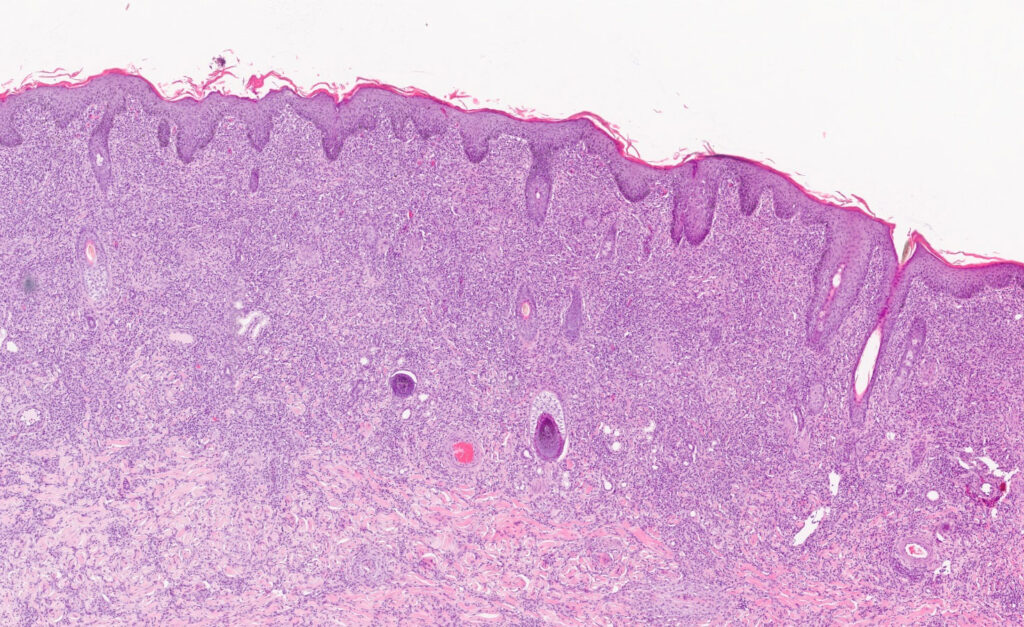

Abb. 2: histologisches Präparat einer diffusen granulomatösen

Entzündung, HE Färbung, 20fache Vergrößerung

Bildquelle: Laboklin

Da andere entzündliche Hautveränderungen wie z. B. Pemphigus foliaceus, coronary band dystrophy, Dermatophilose oder multisystemic eosinophilic epitheliotropic disease (MEED) Sarkoidose klinisch ähneln können, wird für die Diagnose einer LES eine pathohistologische Untersuchung von multiplen Hautstanzen empfohlen. Diese zeigen neben einer epidermalen Hyperplasie und Hyperkeratose eine hochgradige diffuse oberflächliche bis tiefe granulomatöse Dermatitis (Abb. 2). Makrophagen und mehrkernige Riesenzellen dominieren die Entzündungsreaktion. Ferner sind Lymphozyten, Plasmazellen und neutrophile Granulozyten beteiligt. Spezialfärbungen für Pilze und Bakterien (einschließlich säurefester Organismen) verlaufen negativ.